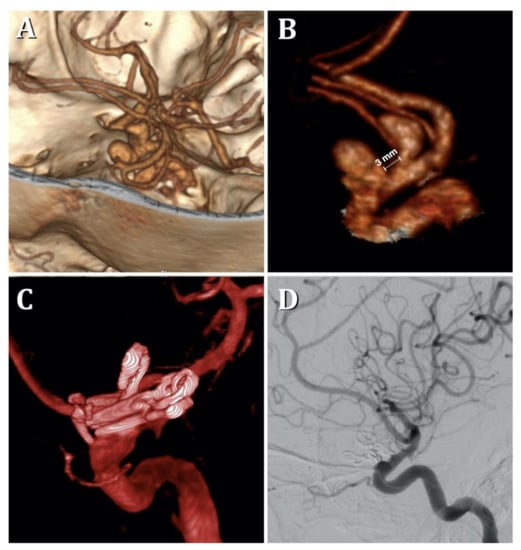

Microsurgical Clipping of Carotid-Ophthalmic Tandem Aneurysms: Case Report and Surgical Nuances

Costa, M.; Baldoncini, M.; Tataryn, Z.L.; Demichelis, M.E.; Conde, A.; Purves, C.; Giotta Lucifero, A.; Hernesniemi, J.; Luzzi, S. Microsurgical Clipping of Carotid-Ophthalmic Tandem Aneurysms: Case Report and Surgical Nuances. Medicina 2021, 57, 731. https://doi.org/10.3390/medicina57070731